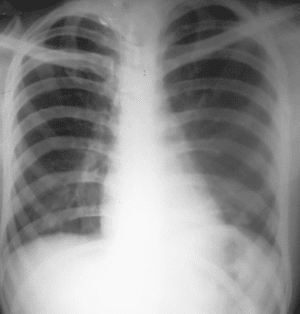

Figura 6. Radiografía Tele de tórax posoperatoria. Dentro de límites normales con buena disposición de las estructuras, se aprecia cuerpo extraño metálico (alambre quirúrgico).